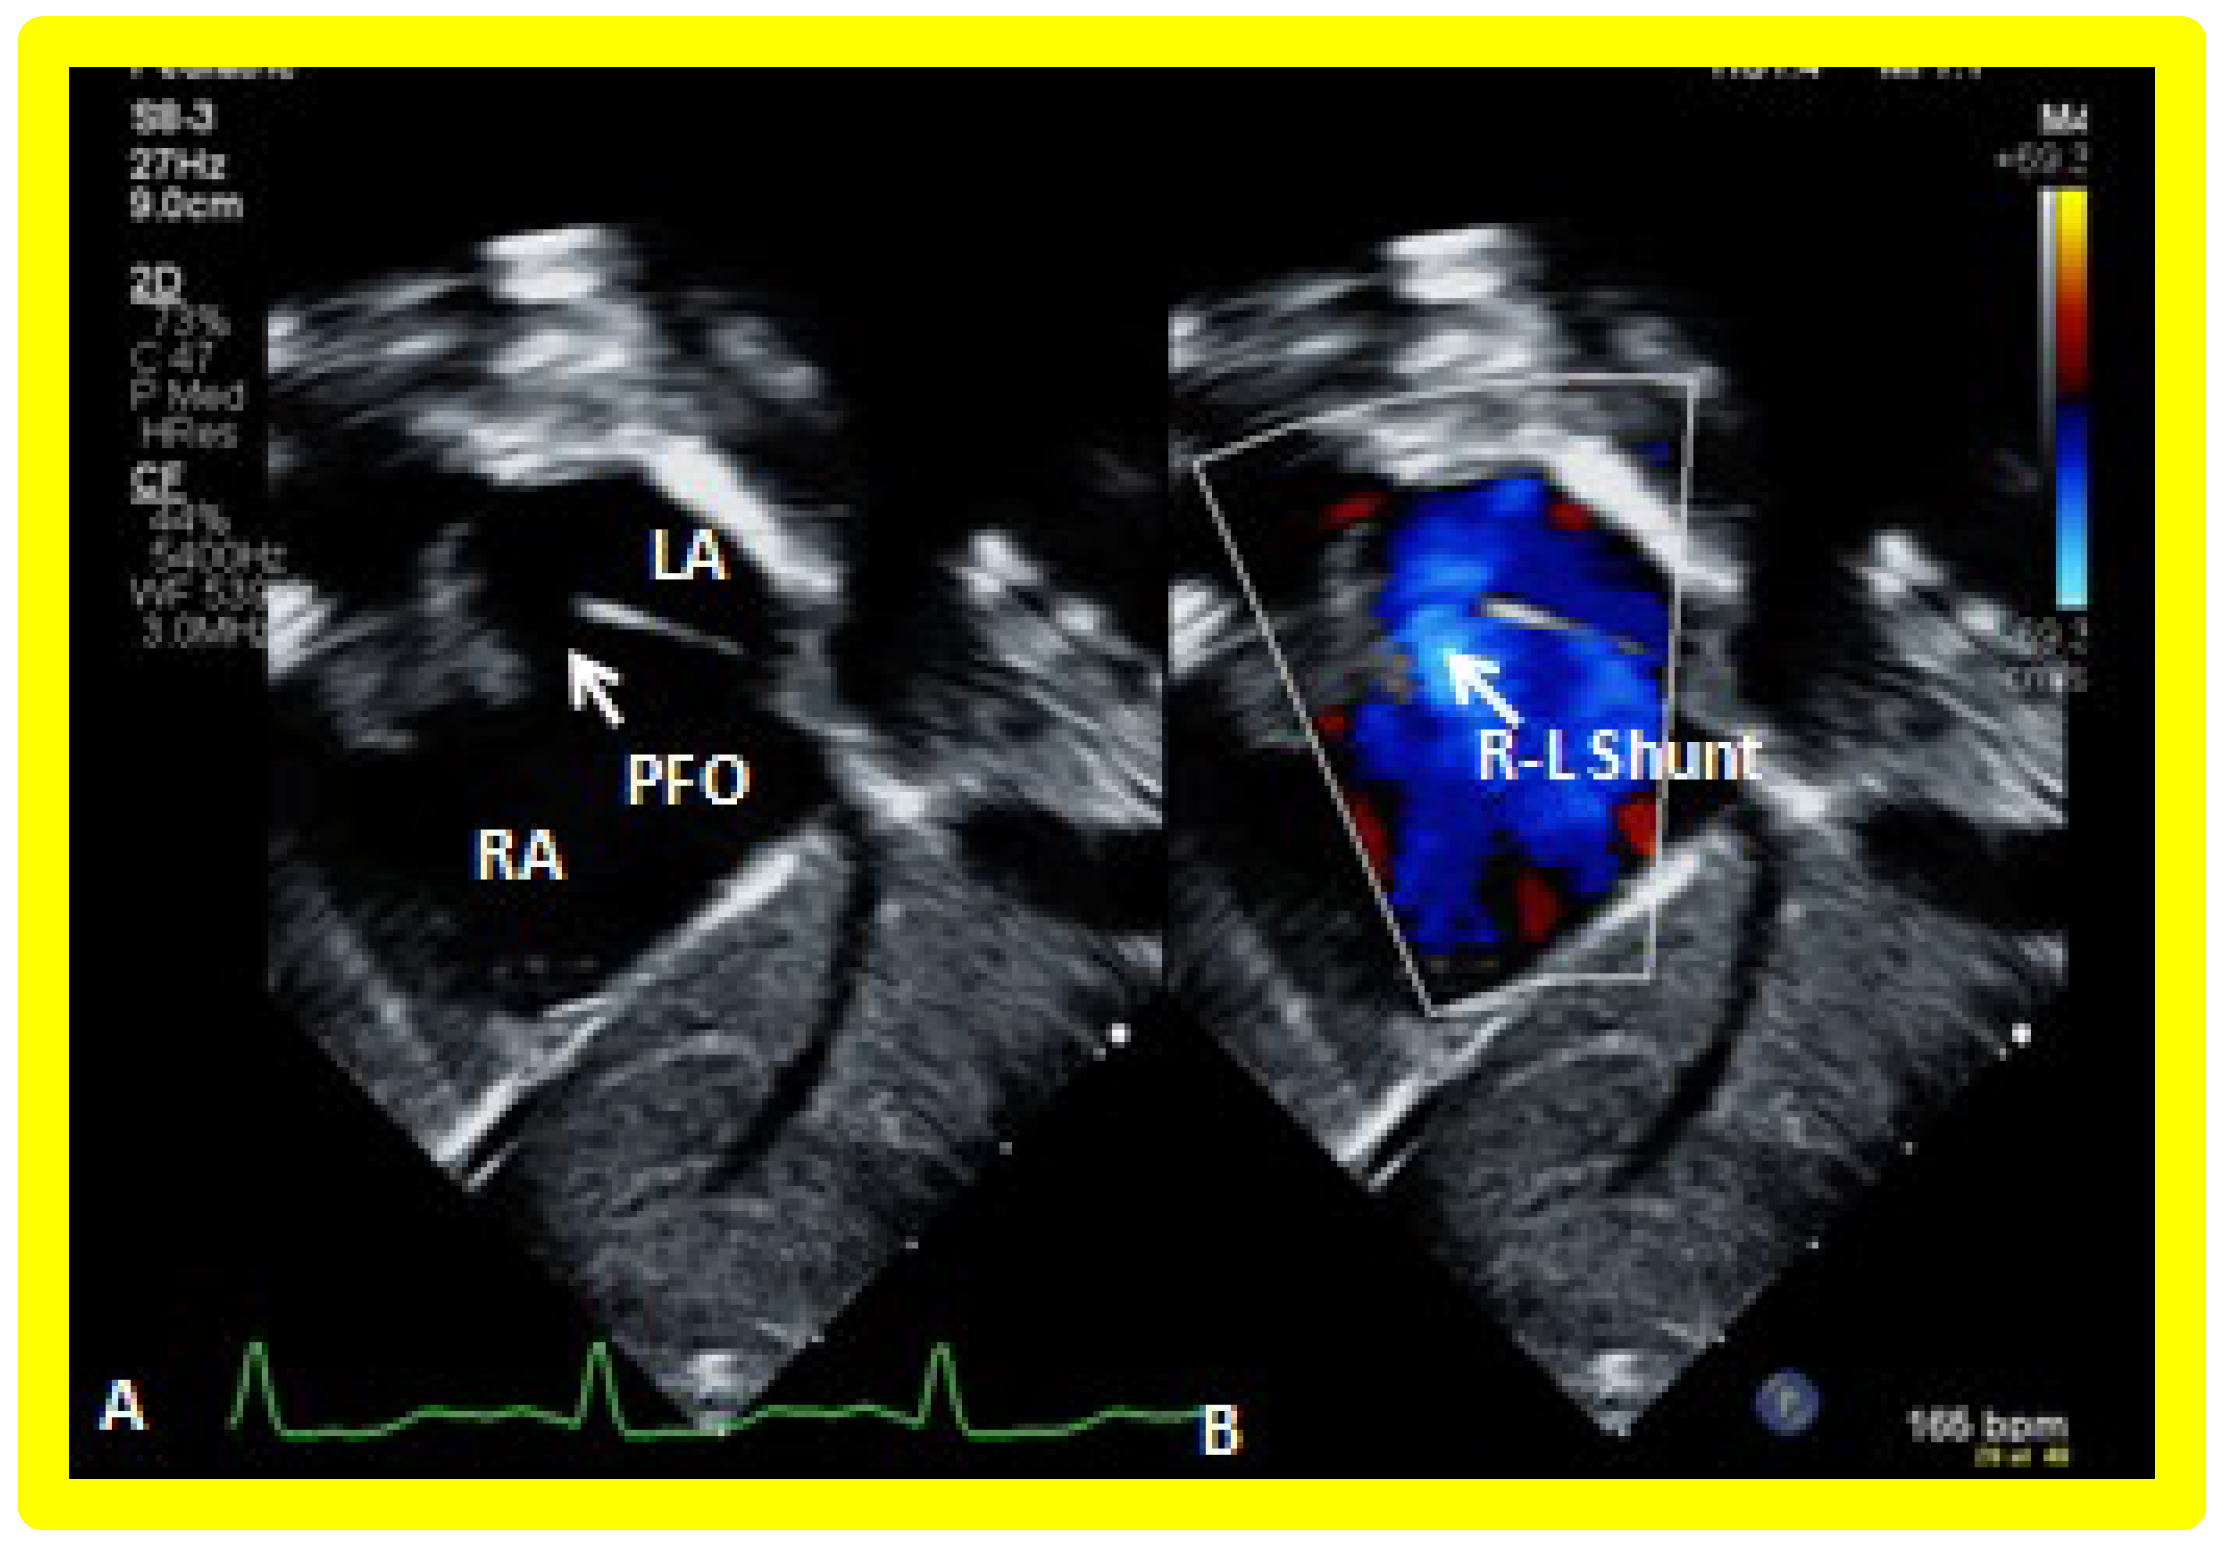

5.2.2. Adequacy of the ASD/PFO

Echo-Doppler studies should examine the adequacy of PFO/ASD to decompress the RA and allow unrestricted flow across it. In the majority of TA patients, the PFO/ASD remains wide open with unrestricted right to left shunt across it with laminar flow (Figure 18). This appears to be secondary to the persistence of fetal circulatory pathways. Only rarely does significant obstruction requiring intervention develop.

5.4.1. Restrictive Inter-Atrial Communication

The adequacy of ASD/PFO in decompressing the RA should be evaluated; the presence of a wide open atrial defect with nonturbulent (laminar) flow across the atrial septum (Figure 18) should be demonstrated. It should be noted, however, that inter-atrial obstruction is more common in patients with hypoplastic syndrome, and its variants, than in subjects with TA. If 2D narrowing along with turbulent and/or high Doppler velocity across the PFO is seen, appropriate transcatheter or surgical relief [38,47] should be provided.

Figure 18. Selected video frames from a subcostal echocardiographic study demonstrating patent foramen ovale (PFO) (arrow in (A)) with right to left shunt (R-L Shunt) across the PFO (arrow in (B)). Note laminar flow across the PFO in B. LA, left atrium, RA, right atrium.